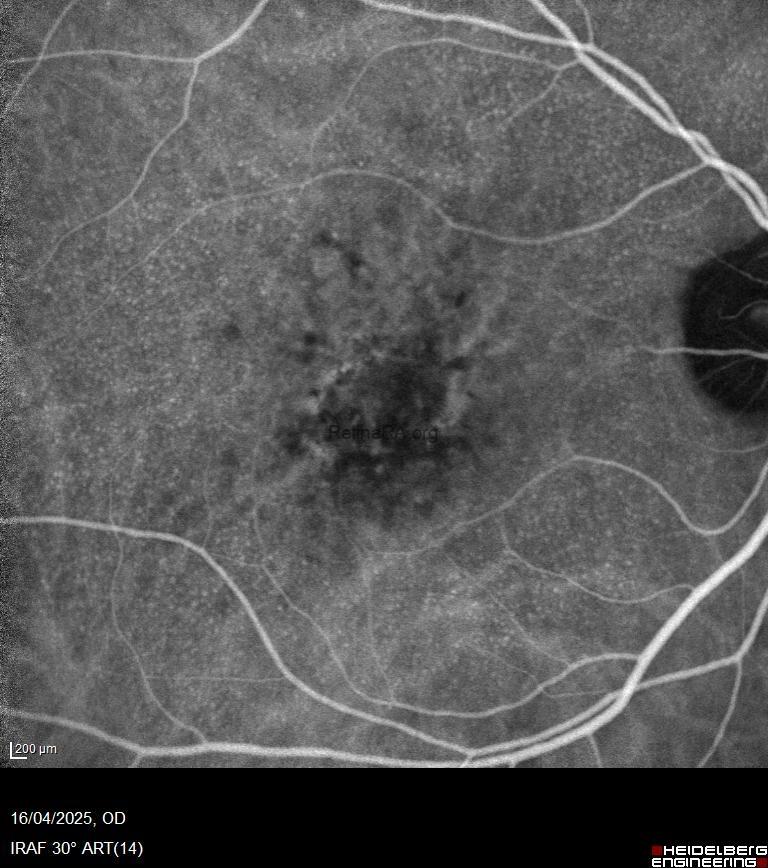

* Fundus Fluorescein Angiography (FFA/FAG):

Exhibits a characteristic “starry-sky” or “milky-way” pattern, with numerous, small, round hyperfluorescent lesions appearing during the intermediate or arteriovenous phase.

The most notable clinical association is the presence of acquired vitelliform lesions (AVLs) in the foveal region (Gass, 1985). Eyes with cuticular drusen are also at increased risk for developing large drusen and choroidal neovascularization (CNV), particularly type 1 CNV.